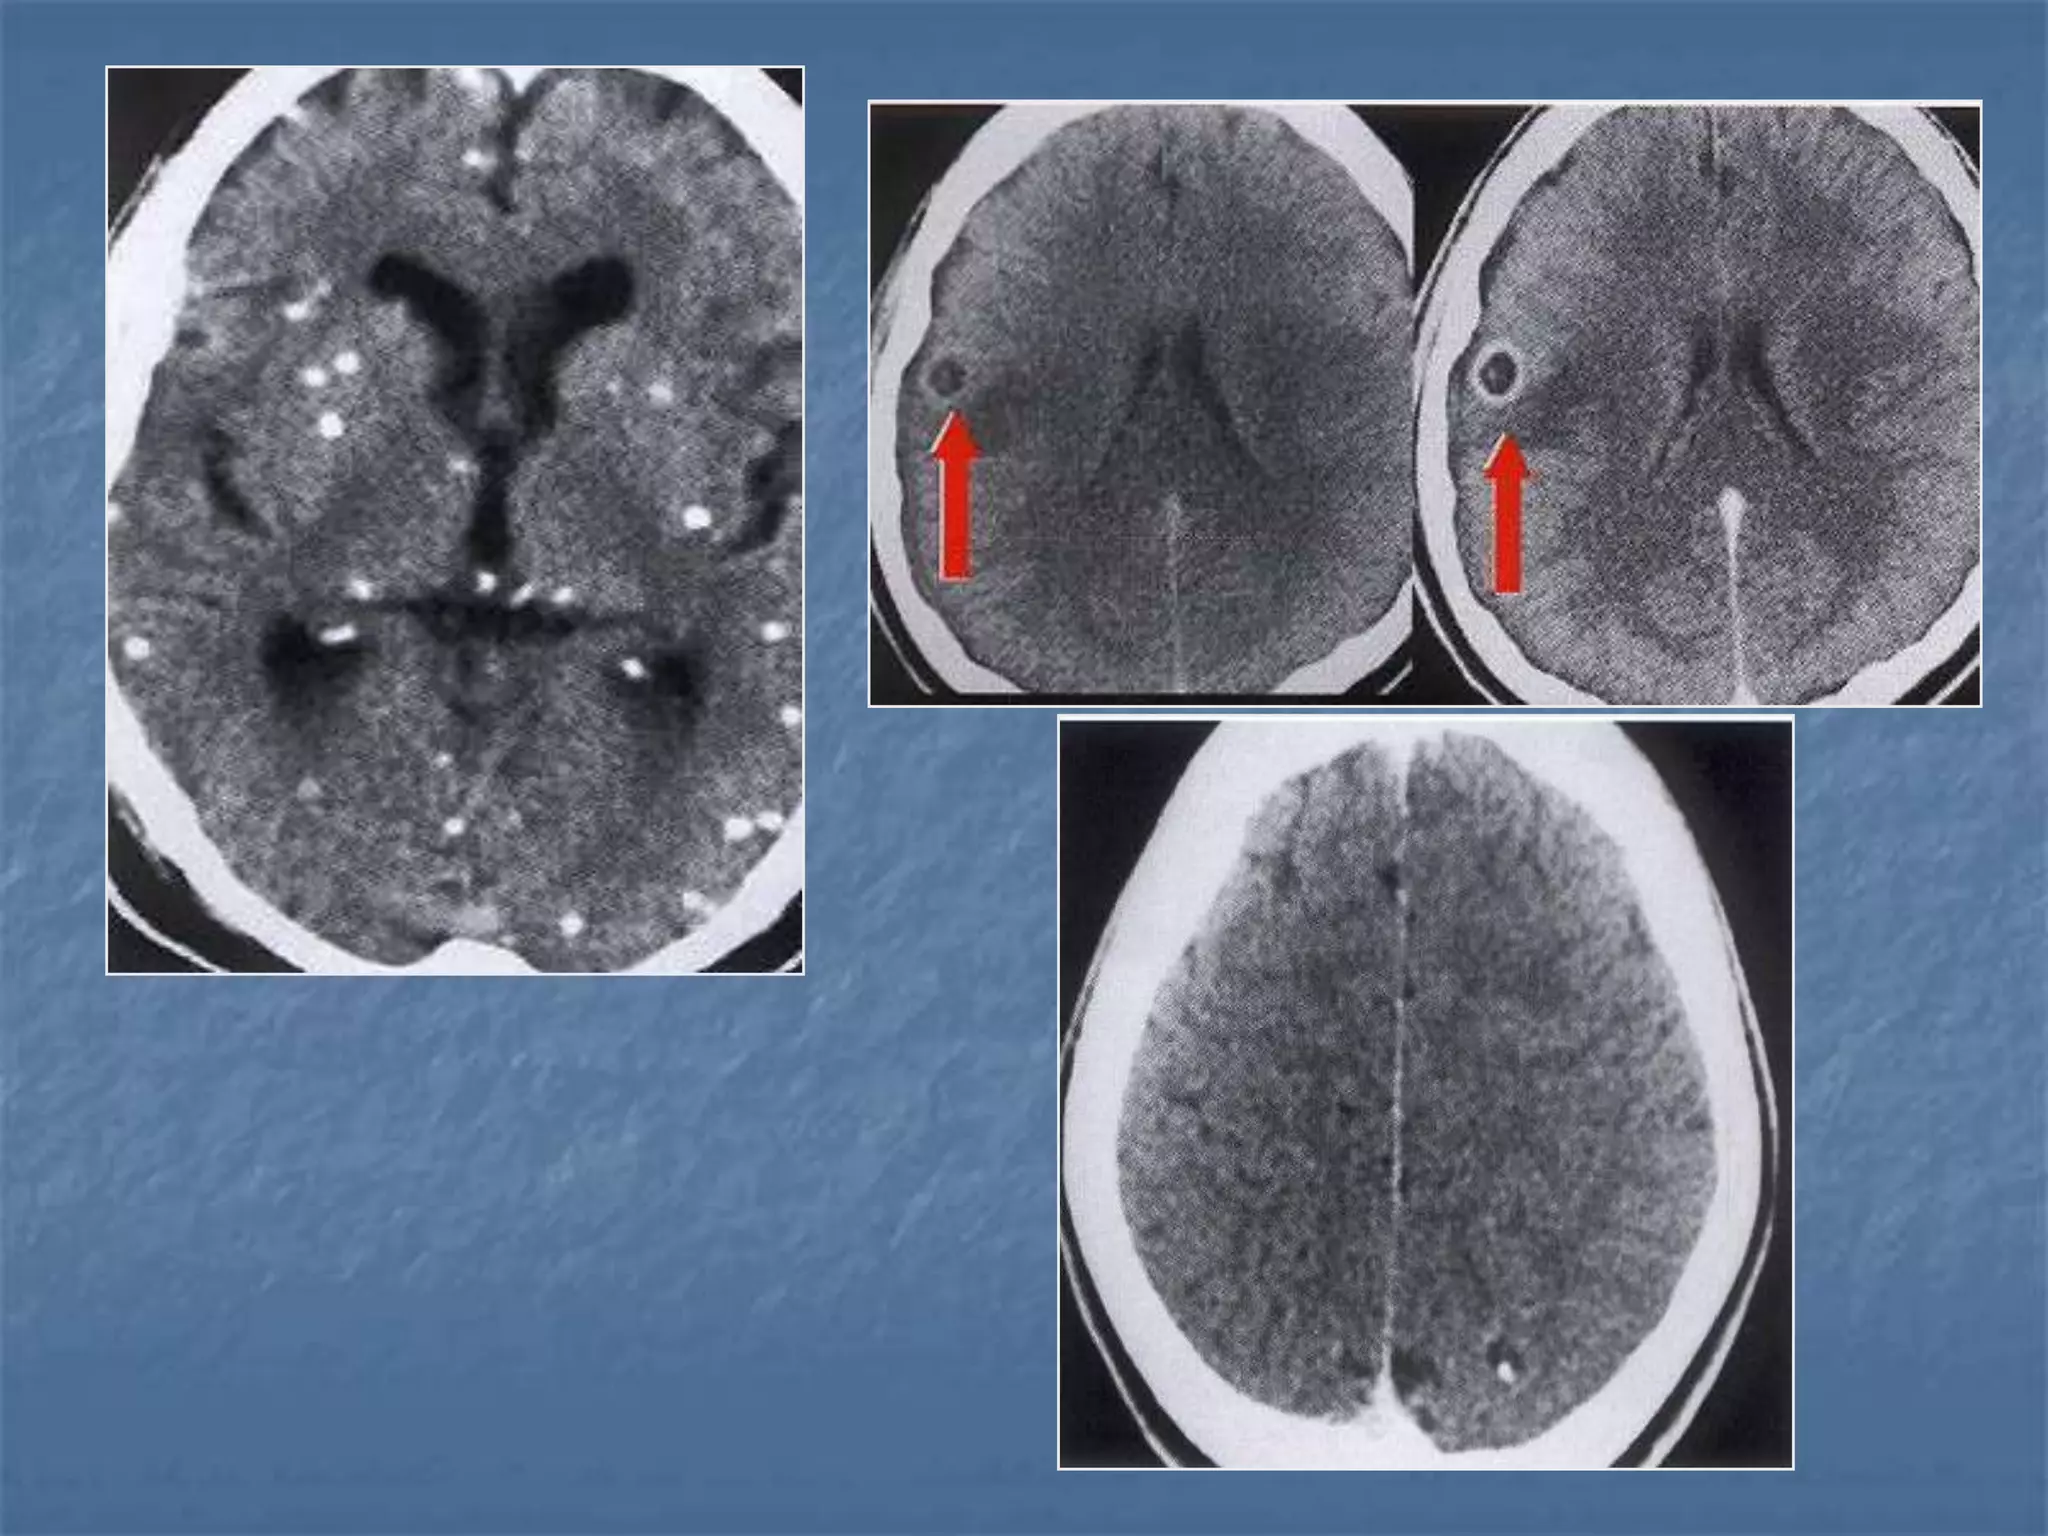

23 yr old male c/o fever and intense headache

 Ring enhancing lesions – granuloma /

abscess

 Calcifications

 Cerebritis

 Meningeal abnormalities

 Complications

Differential Diagnosis of Ring

Enhancing Lesions

 Granulomas

 Brain abscess

 Tumors – metastasis,

glioma

 Resolving hematoma

Encephalitis